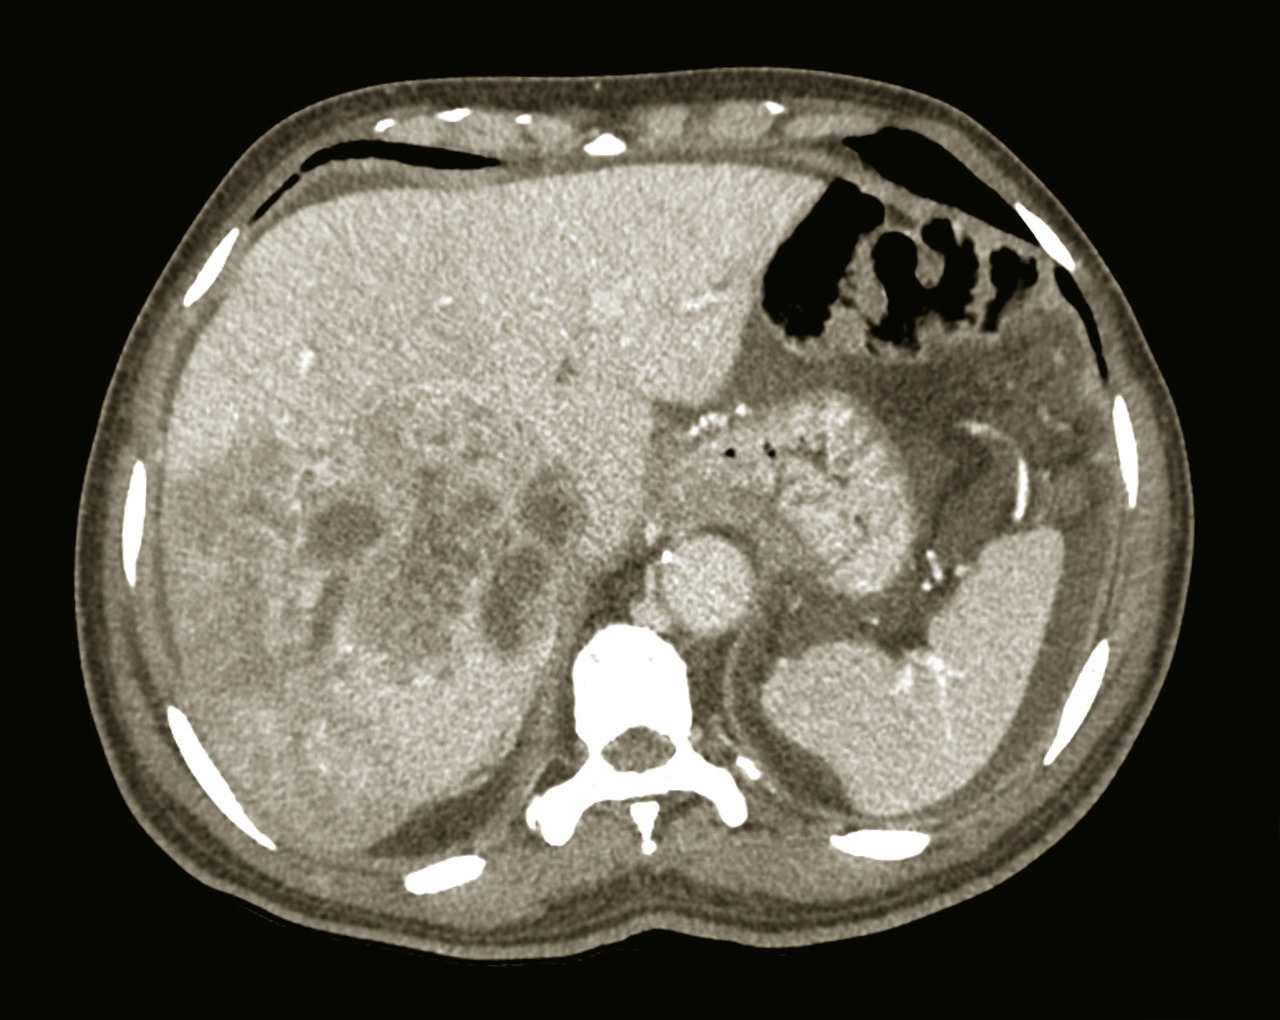

Une imagerie en coupe, tomodensitométrie (TDM) ou imagerie par résonance magnétique (IRM), avec étude triphasique (temps artériel, portal et tardif) après injection de produit de contraste, peut être utile au diagnostic étiologique d’une hépatomégalie.